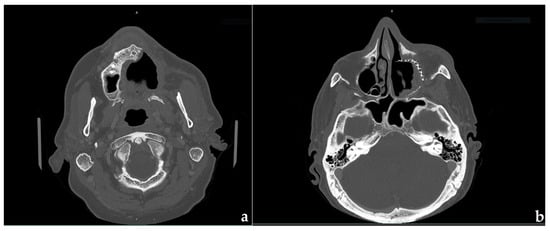

2. Clinical Case Presentation

2.1. Surgical Procedures